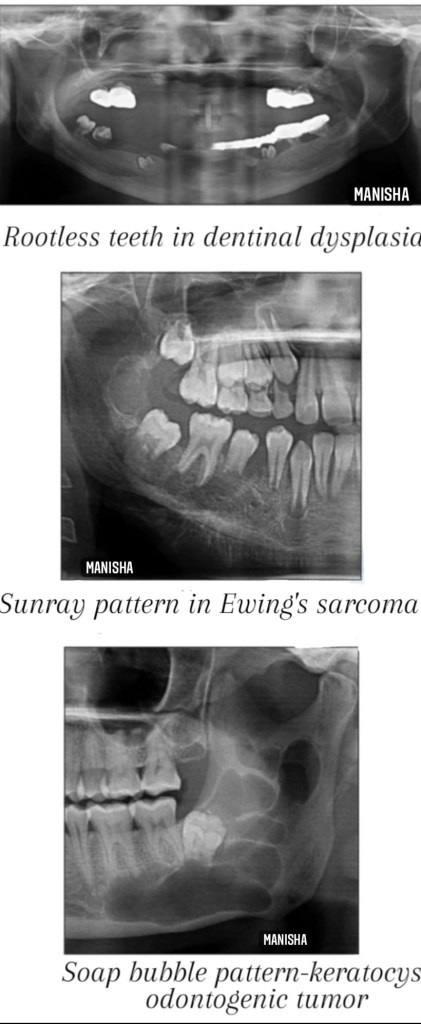

- Rootless teeth appearance-dentinal dysplasia

- Soap bubble appearance-ameloblastoma,aneurysmal bone cyst,central hemangioma,central giant cell granuloma, odontogrnic keratocyst

- Sunburst/sunray appearance-central hemangioma,osteosarcoma,Ewing’s sarcoma